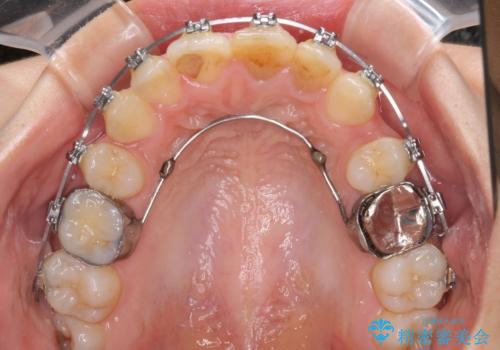

- 矯正装置

- メタルブラケット

- 治療期間

- 2年6ヶ月

受け口傾向の方の下顎抜歯矯正では、下顎前歯の歯肉が退縮することがあります。前歯を移動させるときには、歯肉退縮が起こらないように工夫する必要があります。